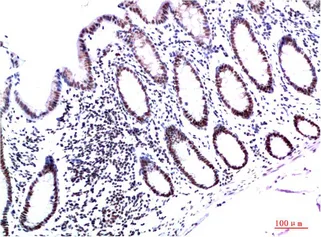

CK7(12D7)Mouse Monoclonal Antibody

Cat: AMM08857

Size1:50μl Price1:$128

Size2:100μl Price2:$230

Size3:500μl Price3:$980

Size2:100μl Price2:$230

Size3:500μl Price3:$980